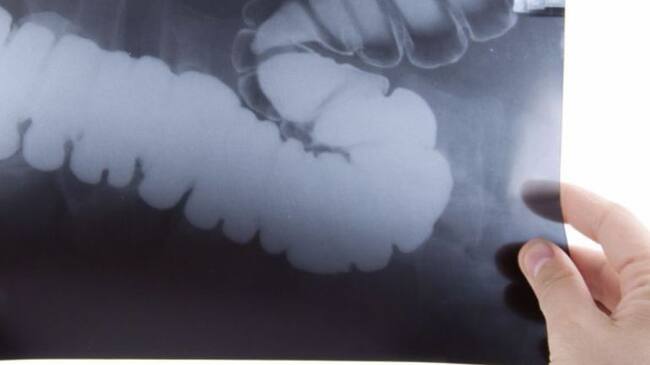

Radiografía / Cadena SER

La AECC incluye a Huelva en situación "crítica" por cáncer de colon

La Asociación Española contra el Cáncer (AECC) señala a Huelva, entre otras siete provincias españolas, bajo una situación crítica por la incidencia o mortalidad del cáncer de colón. La asociación advierte que siete millones de personas en edad de riesgo de padecer cáncer de colon, entre 50 y 69 años, continúa sin acceso a los programas de cribado, y que Cantabria es un "punto negro" en ese sentido.

Asimismo, subraya en una nota que las provincias españolas de Badajoz, Cáceres, Asturias, Cantabria, Huelva, Sevilla y Córdoba y la ciudad autónoma de Melilla se encuentra "en situación crítica", porque la incidencia o mortalidad del cáncer de colon está por encima de la media española.